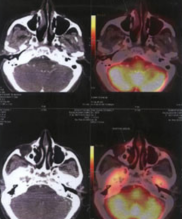

Ewing’s Sarcoma

INITIAL STAGE

10-Feb-2009

Before Treatment :

Scan findings consistent with multiple skeletal mets from Ewing’s Sarcoma.

X-Ray DURING HERBAL ONCOLOGY

01-Aug-2009

Absence of viable tumour

X-RAY AFTER HERBAL ONCOLOGY

04-Sep-2009

AfterTreatment :

No Focus abnormally increased FDG uptake to suggest metabolically active disease on the present study